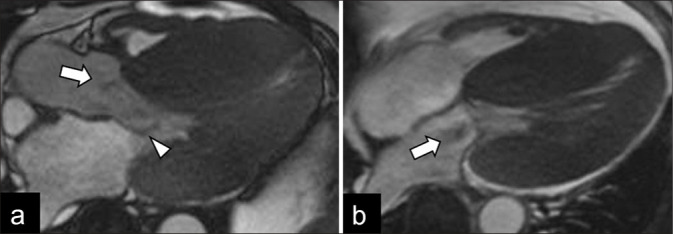

Fabry disease (FD) is a rare X-linked lysosomal storage disorder. Cardiac involvement is frequent in the classic phenotype and late-onset cardiac variant of FD. It is challenging to distinguish FD cardiomyopathy from other forms of unexplained left ventricular hypertrophy, especially in those patients without extracardiac manifestations. Cardiac magnetic resonance imaging is an essential imaging modality for the quantitative and qualitative assessment of FD cardiomyopathy. It helps to monitor disease progress and allows early disease detection in the mild form or subclinical cardiac phenotypes. This review illustrates the characteristic imaging features of FD cardiomyopathy in cardiac MRI, aiming to enhance the awareness of this disease entity among the scope of unexplained cardiomyopathy and promote timely enzyme replacement therapy for patients.